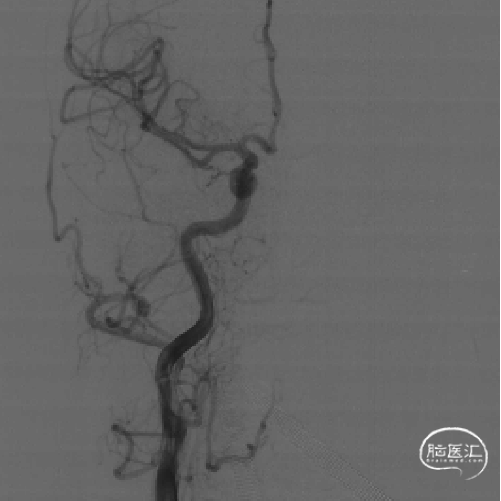

DSA评估:右侧颈内动脉末端闭塞,颈内动脉走行迂曲

DSA评估:前交通开放,左侧颈内动脉通过前交通动脉向右侧大脑前动脉代偿供血,并逆向充盈至右侧大脑前动脉A1段

DSA评估:后循环未见明显向右侧颈内动脉供血区代偿供血

DSA提示右侧颈内动脉末端闭塞,局部可见“杯口”征;左侧颈内动脉通过前交通代偿,并逆向充盈至右侧A1段;该患者为颈内动脉末端“T”型闭塞。结合房颤病史,病因分型为心源性栓塞。

影像学随访

术后第5天复查脑CTA:右侧颈内动脉、大脑中动脉、大脑前动脉通畅